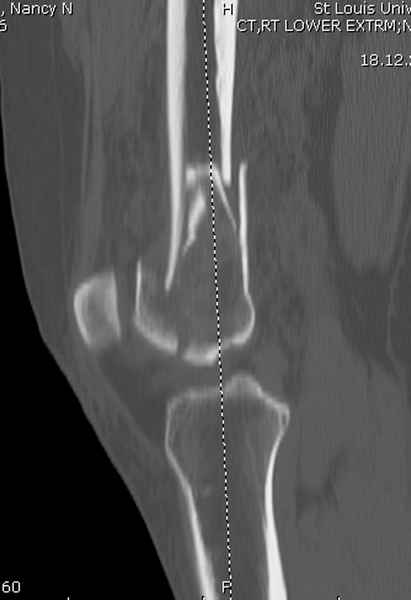

При наличии различных имплантов, любые варианты: слева (полу) открытым - мининвазивным, а справа закрытым интрамедуллярным методом, его считаем более чем приемлемым для фиксации данных переломов.

Проксимальная и дистальная блокировка, независимо от техники введения штифта, ретроградно или антеградно, гарантирует сращение сегментарных переломов бедра без укорочения. Штифты диаметром 12 мм с блокировкой сверху и вниз двумя шурупами выдерживают вес 75 кг больного, что позволяет раннюю профилактику контрактур.

Погоня за "красивой рентгенограммой" не всегда оправдана для фиксации кости, где имеется массивное мягкотканое покрытие. Если так уж хочется исправить положение кости, то при наличии ЭОП, большие костные фрагменты могут быть развернуты или приближены к основному фрагменту методом применения Joystick.

Главное в лечении сегментарных переломов - необходима осторожность при рассверливании канала, продвижение гибкого сверло через сегмент проводят без сверления, толканием, а то были случаи, когда весь сегмент крутился вместе со сверлом.

Из-за вариабельности установки дистальных шурупов и возможности перкутанного введения проксимально предпочитаем DePuy Polyax, хотя на сегодняшнем маркете множеств вариантов фиксации дистального бедра перкутанном методом.